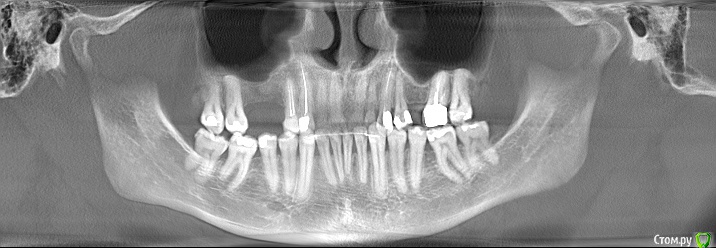

Дмитрий-Р Опубликовано 4 апреля, 2016 Поделиться Опубликовано 4 апреля, 2016 Здравствуйте, после 2-х консультаций немогу выбрать к кому идти. Ситуация такая: необходимы 2 импланта справа вверху (1,6 и 1,5). Год назад, в этом месте, были удалены два корня и осуществлена (сразу) пластика коллапаном. Врач №1. Синуслифтинг не нужен, ставим 1,6 (35 L=6 мм) и 1,5 (35 L=9 мм). Система Астра Техн. Врач №2. Сперва открытый синуслифтинг искусственной костью и одномоментно расширение десны (+подсадка ткани на впалую часть десны со стороны щеки). Системы 3-i? Impro, MIS, Inno. Подскажите пожалуйста, какой путь выбрать? Может быть искать 3-й вариант? Ссылка на комментарий

red_butler Опубликовано 4 апреля, 2016 Поделиться Опубликовано 4 апреля, 2016 нужно больше информации. Покажите срезы области интереса. Я бы скорее всего рассматривал закрытый синуслифтинг 3 Ссылка на комментарий

red_butler Опубликовано 6 апреля, 2016 Поделиться Опубликовано 6 апреля, 2016 Стандартов нет. Выбор методики антральной аугментации диктуется объемом кости в вертикальном направлении. Для меня желаемая длина импланта на в/челюсти 9-11 мм, реже 8 мм. Если кости до дна 2 Ссылка на комментарий